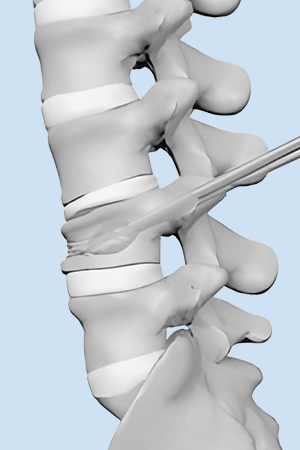

בלון kyphoplasty הוא הליך זעיר פולשני שנועד לתקן שברי דחיסה בחוליות על ידי צמצום וייצוב השבר. הוא מטפל בשברים פתולוגיים של גוף החוליה עקב אוסטאופורוזיס, סרטן או נגעים שפירים.

טיפול סימפטומטי קונבנציונלי כולל משככי כאבים בפה, הקרנות פליאטיביות, ניתוחים וטיפול סיסטמי כגון ביספוספונטים. מטופלים רבים נאבקים בטיפולים אלו עקב ביקורים חוזרים, יעילות ירודה ותופעות לוואי. בשנת 1984, המנתח הצרפתי Galibert דיווח על יישום הזרקת מלט עצם דרך עורית בטיפול בכאב בלתי פתיר הנגרם על ידי המנגיומה השנייה של עמוד השדרה הצווארי, ויצר תקדים להזרקת מלט עצם עורית זעיר פולשנית בטיפול בנגעים בחוליות. תוך 48 שעות לאחר ניתוח ורטרופלסטיה מלעורית (PVP) או קיפופלסטיקה בלון מלעורית (PKP), הקלה משמעותית בכאב הייתה קשורה להפחתת השימוש בתרופות ולשיפור הפרמטרים התפקודיים.